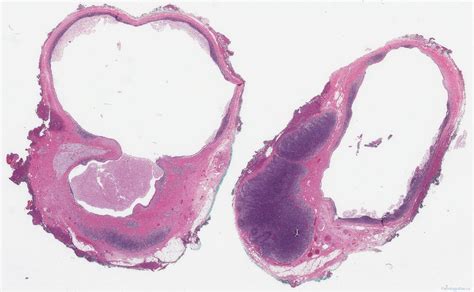

Branchial cleft fistulas are congenital anomalies that result from the incomplete obliteration of the branchial apparatus during embryonic development. These fistulas are typically located in the lateral aspect of the neck and can present with various symptoms, including recurrent infections, discharge, and swelling. Understanding the causes, symptoms, diagnosis, and treatment options for branchial cleft fistulas is crucial for effective management and patient care.

Branchial cleft fistulas are congenital malformations that occur due to the failure of the branchial apparatus to fully develop and close during fetal development. The branchial apparatus consists of a series of arches, clefts, and pouches that give rise to various structures in the head and neck region. When these structures do not properly close, they can result in fistulas, cysts, or sinuses.